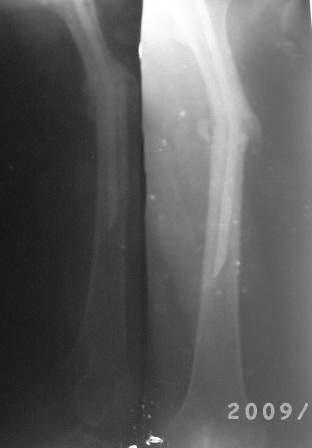

Re: Искривление и/м штифта

Снимки не очень качественные, почему-то все снимки такие . видимо поступило партия некачественных пленок.